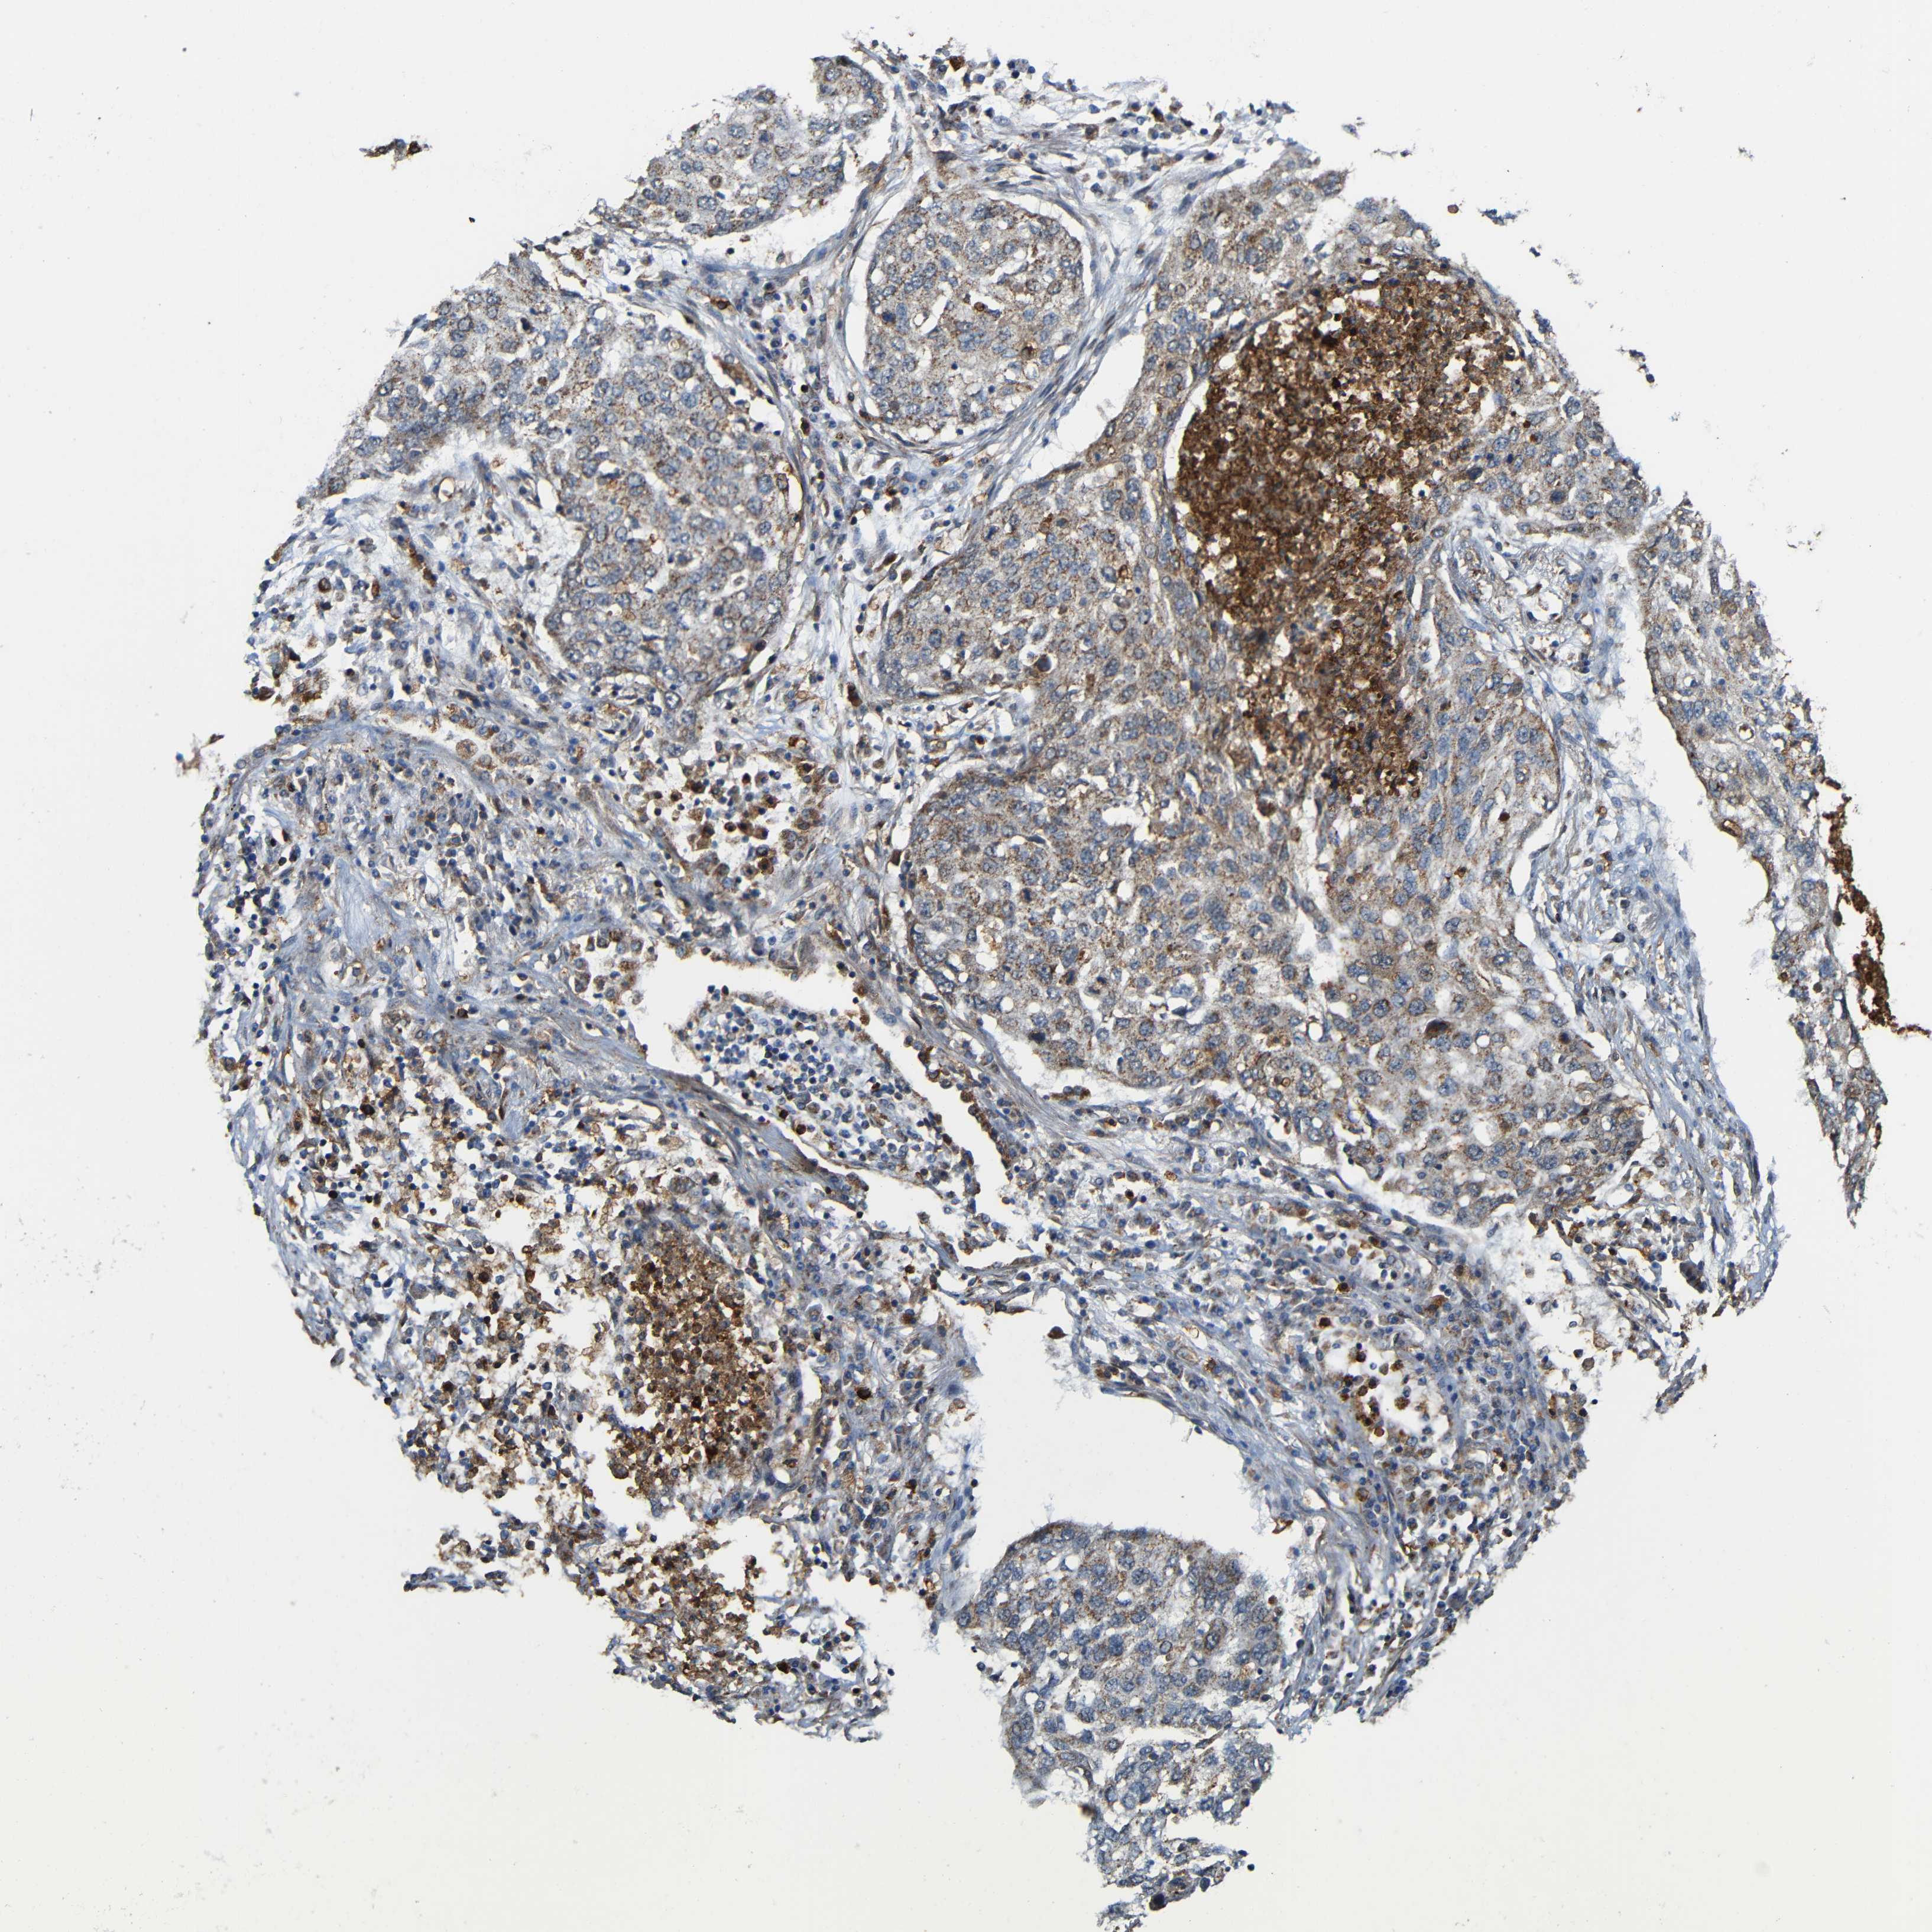

CANCER LUNG CANCER Show tissue menu